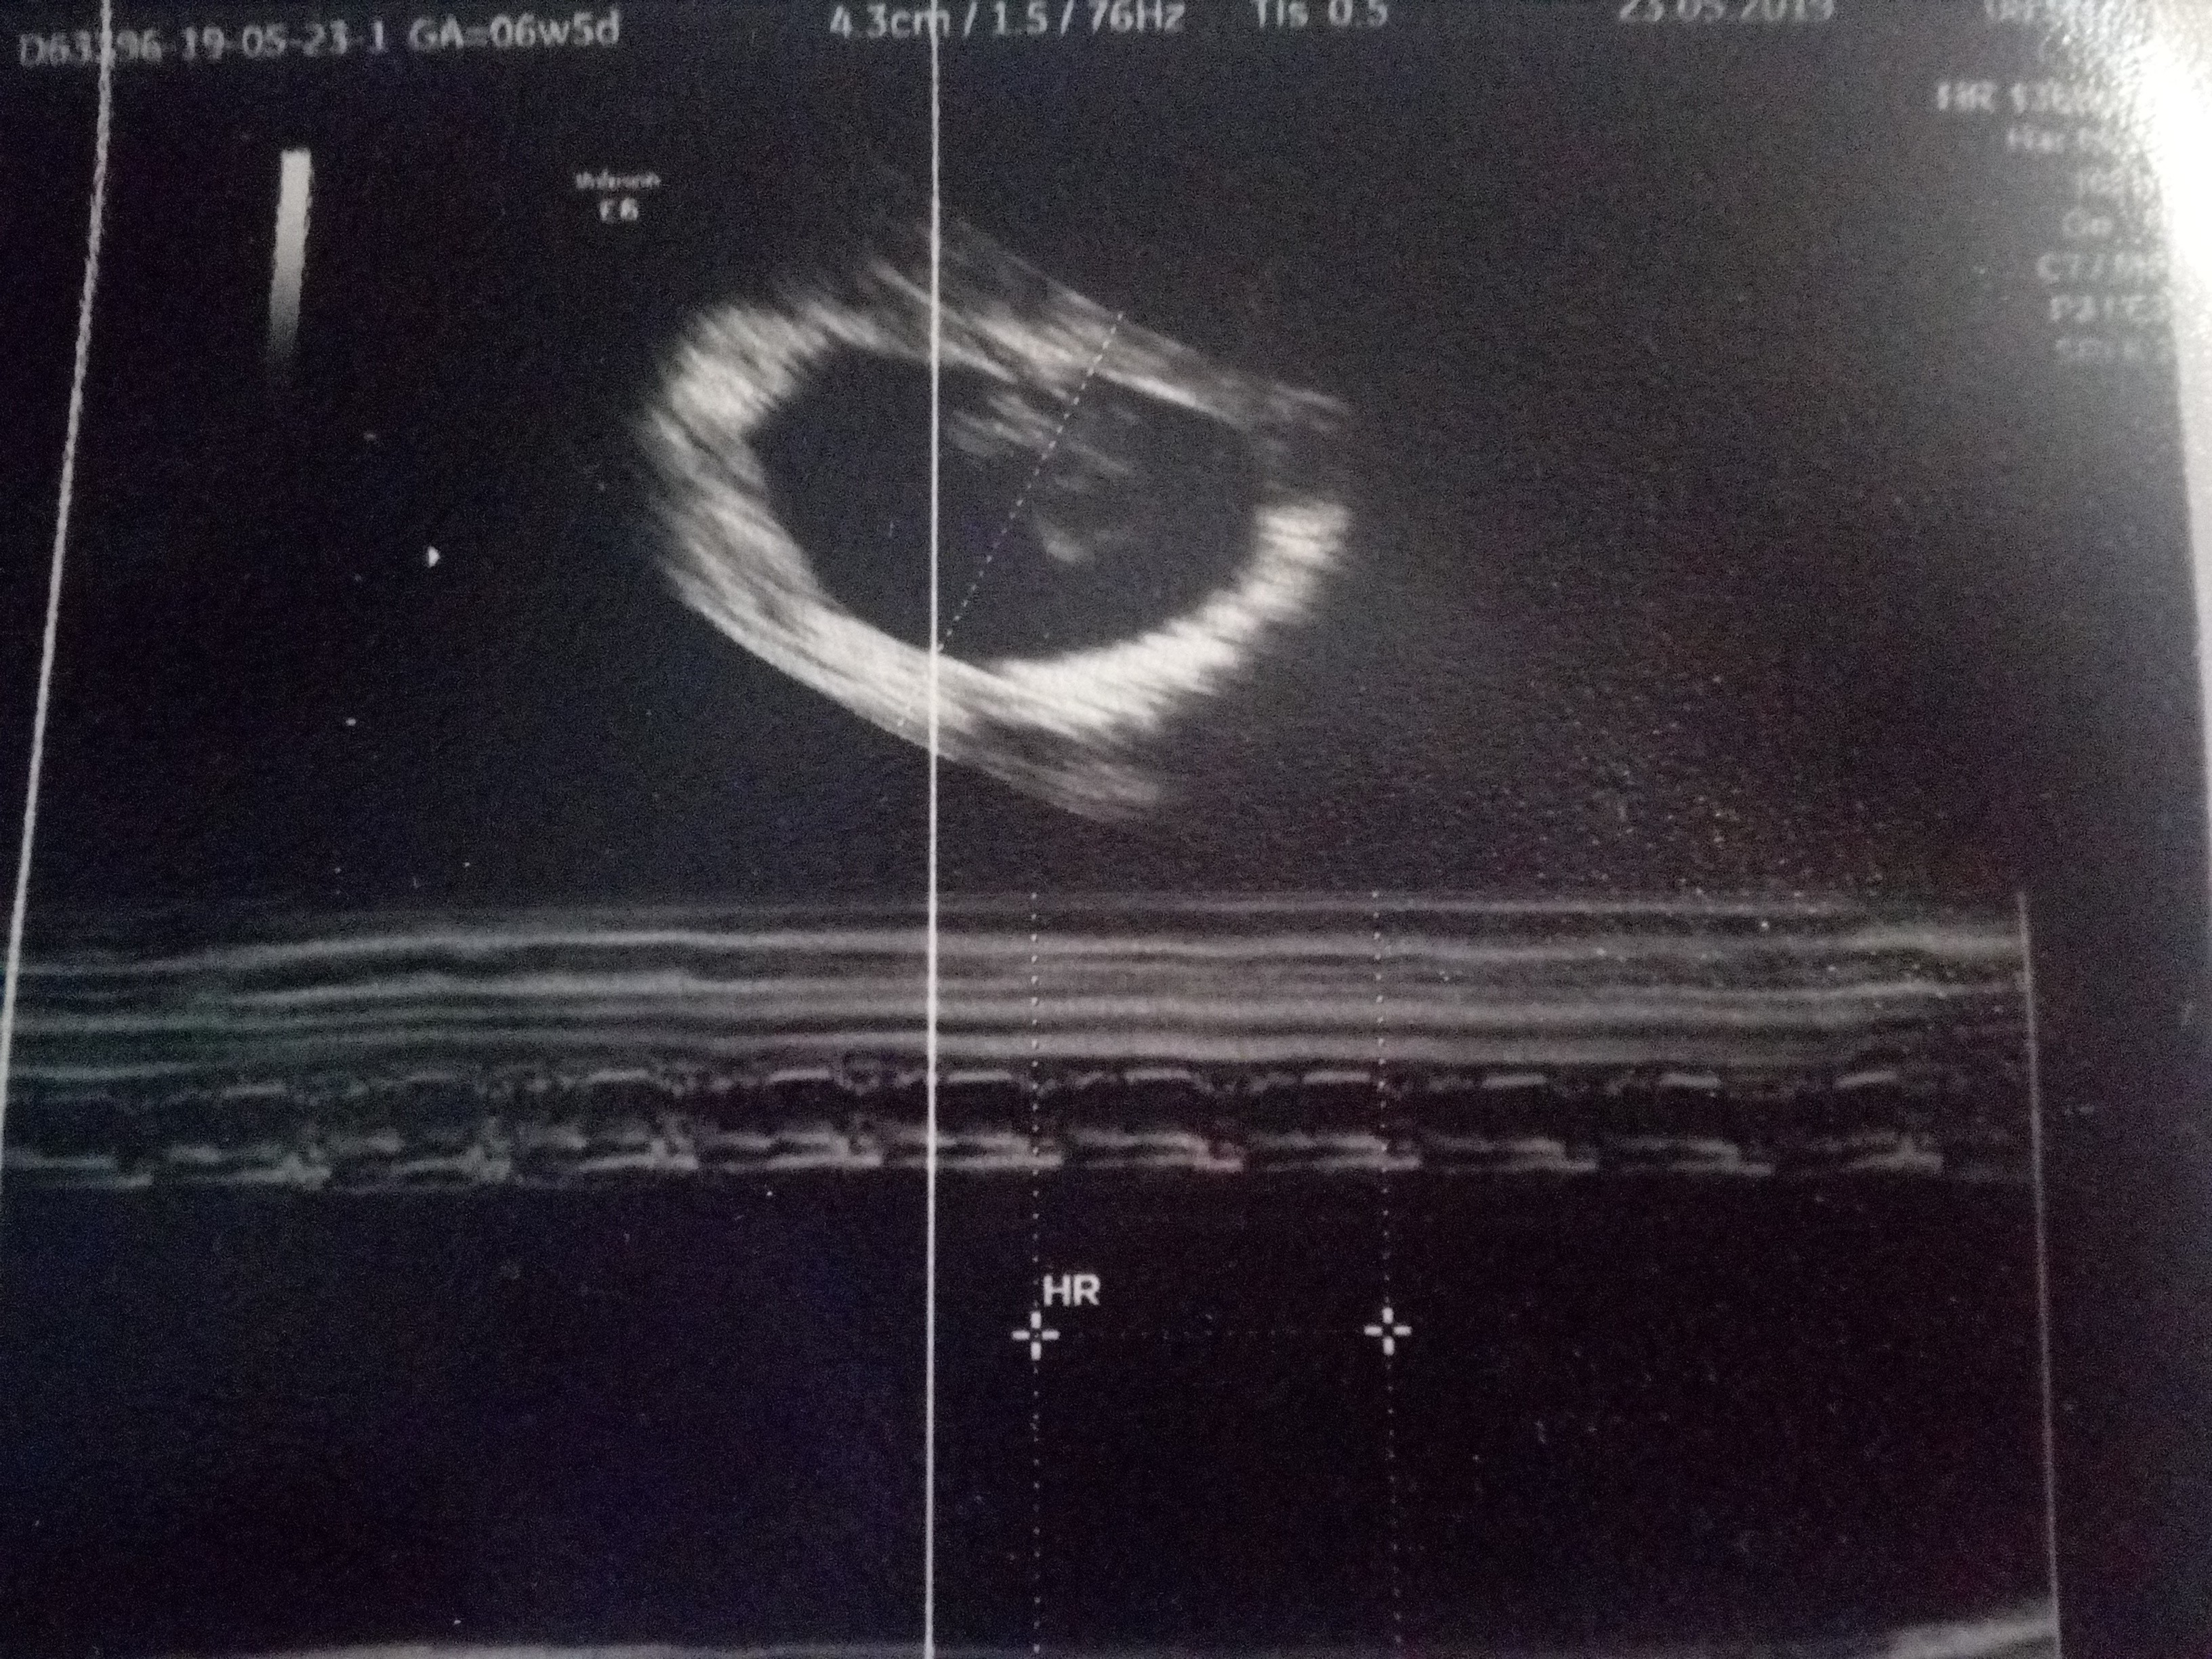

Dziś byłam na wizycie i przedstawiam Moją Fasolkę :D

Wszystko idealnie się zgadza ,serduszko pięknie bije .. oby tak do końca :D

Zdjęcia robione telefonem jakoś jaka jest taka jest ,sypie mi się telefon powoli ;)

Załączniki

• IMG_20190523_173720.jpg

IMG_20190523_173720.jpg

2,6 MB · Wyświetleń: 98